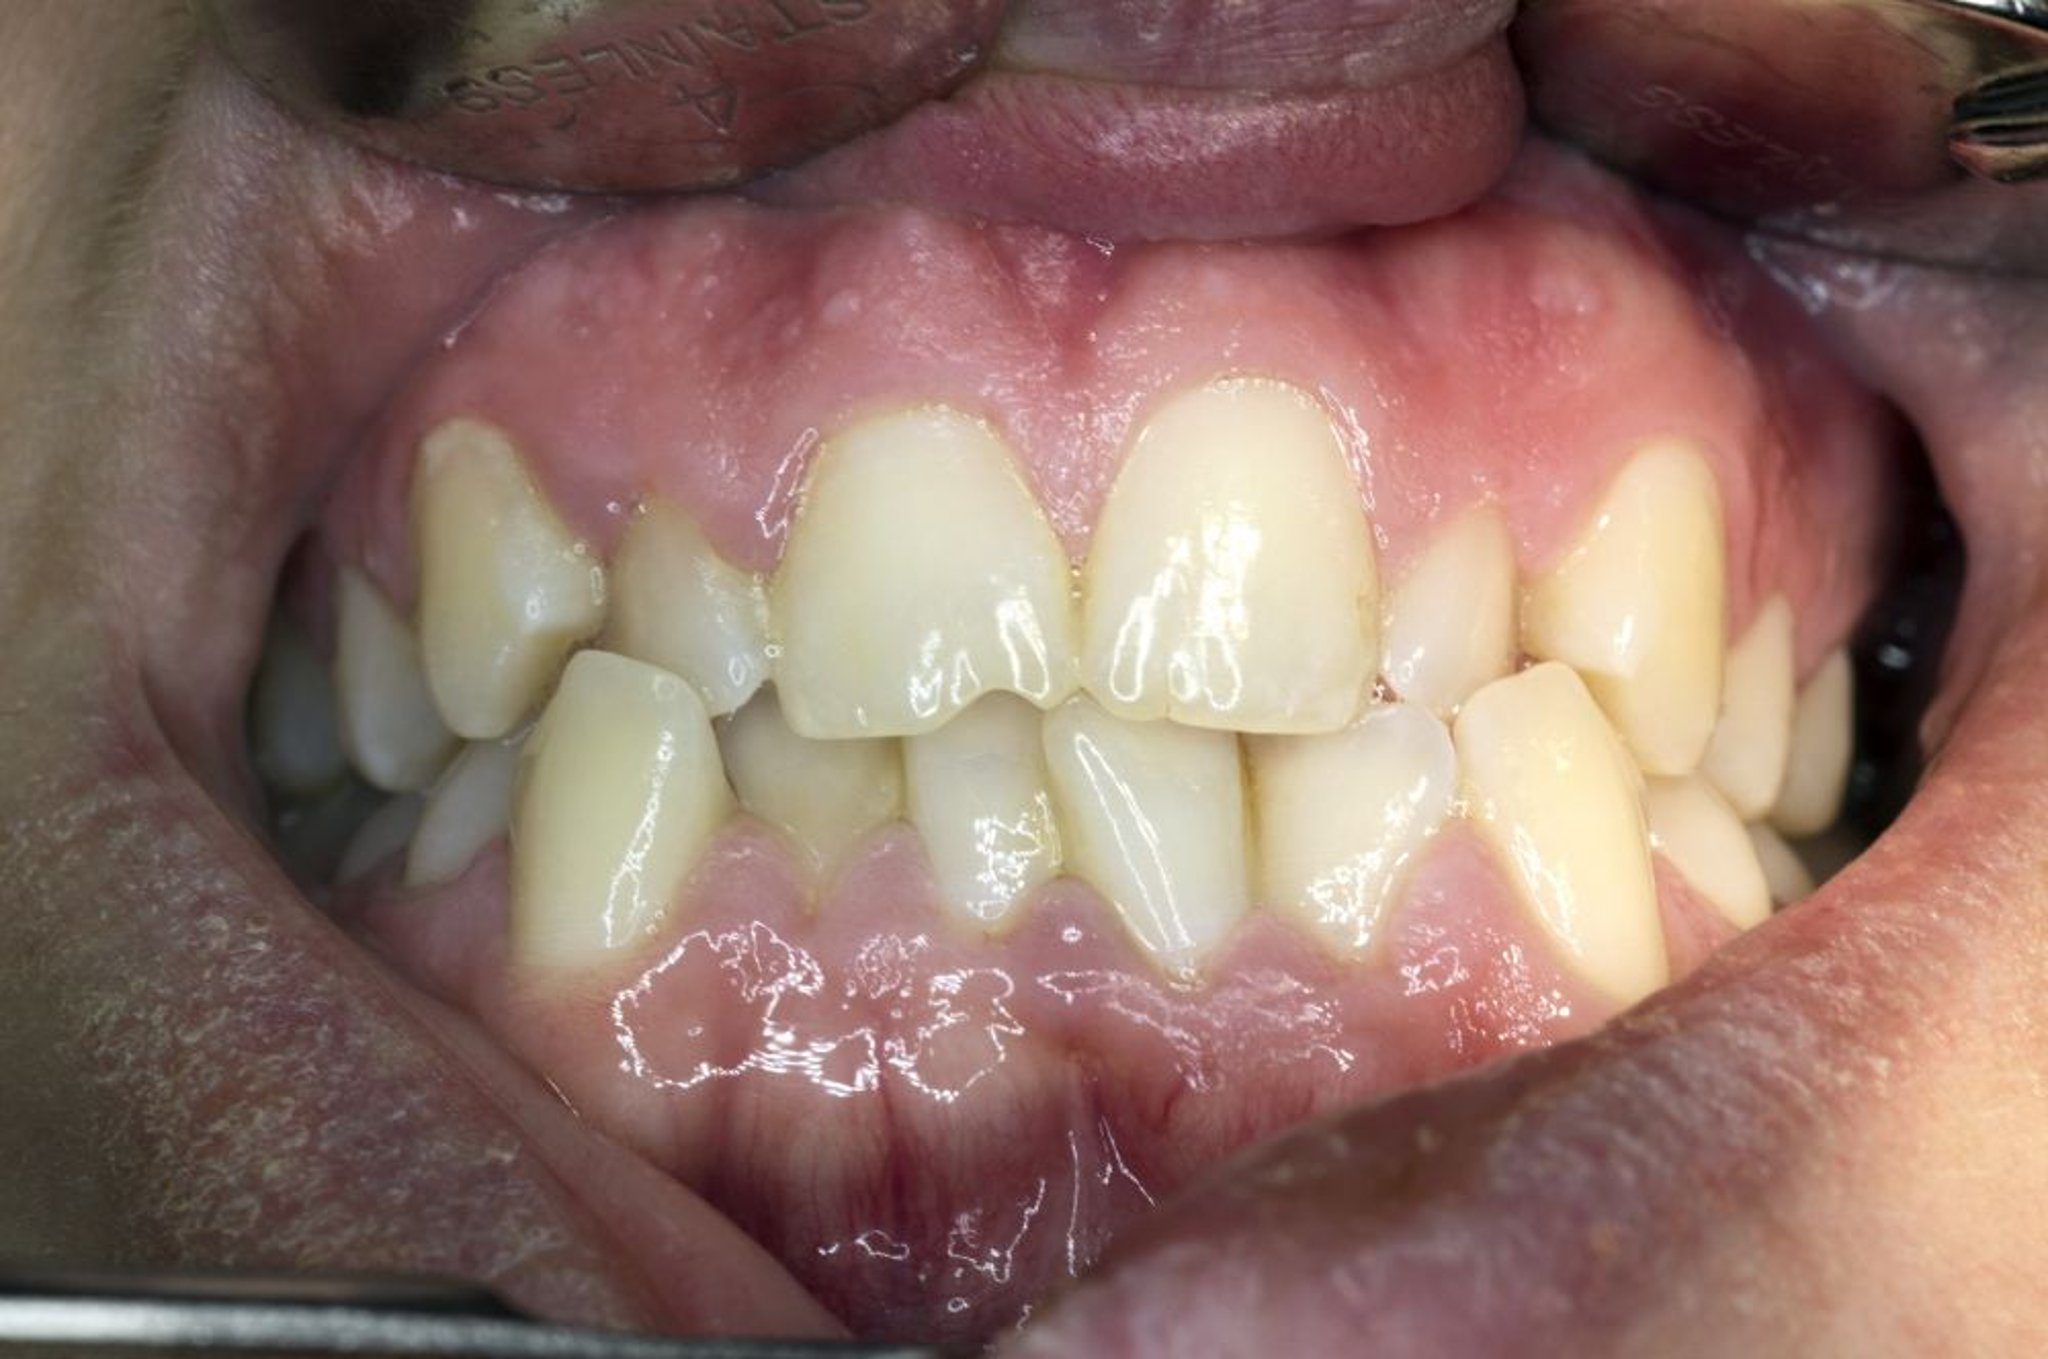

通常,上下歯列弓は隣接する歯と接触して列んでいる状態で,滑らかな曲線を形成し,上顎前歯が下顎前歯の上部3分の1を覆っている(の図を参照)。上顎臼歯群の頬側(外側)咬頭は,対応する下顎臼歯群の咬頭の外側に位置している。ほとんどの場合,上顎の第1大臼歯の近心頬側咬頭は下顎第1大臼歯の近心頬側溝と嵌合している。

患者に臼歯を咬み合わせるよう指示し,舌圧子で頬を牽引しつつ両側の咬合をチェックする;患者に咬むように伝えると患者が誤解して切歯同士で咬み合わせることがあり(果物を咬む時のように),これによって臼歯部の咬合が不正に見えることがある。不正咬合は,最初の歯科受診時(1歳時)という早い段階で同定されることがある。早期の同定により,後の処置をより容易かつ効果的に行うことができる。